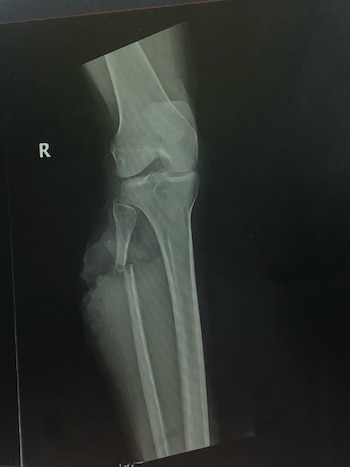

Entonces, Thompson oyó un “ligero revuelo de agua” y vio una pequeña ondulación en su visión periférica. Rápidamente se convirtió en una cabeza de cocodrilo y en un ataque casi instantáneo. Scar le hundió los dientes en la pantorrilla derecha, rompiéndole el peroné.

Los médicos temían que fueran necesarias dos o tres operaciones e injertos de piel para limpiar, cubrir y cerrar la herida. Pero una vez que empezaron a trabajar, determinaron que, aunque tenía una fractura limpia en el peroné y “muchos daños musculares”, el cocodrilo no le había arrancado la piel ni cortado ningún nervio importante.